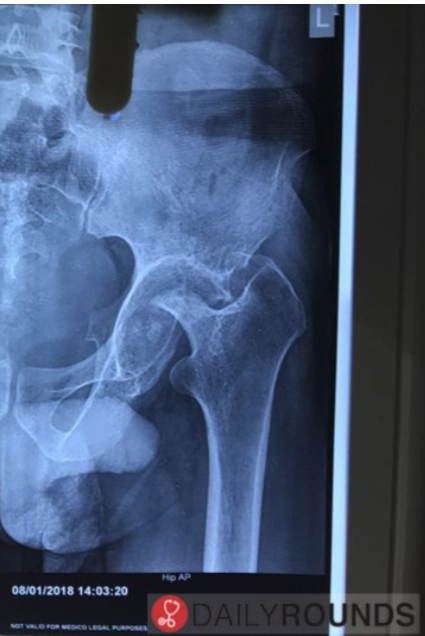

X-ray showing _____ hip are suggestive of tuberculosis (TB) of the hip\